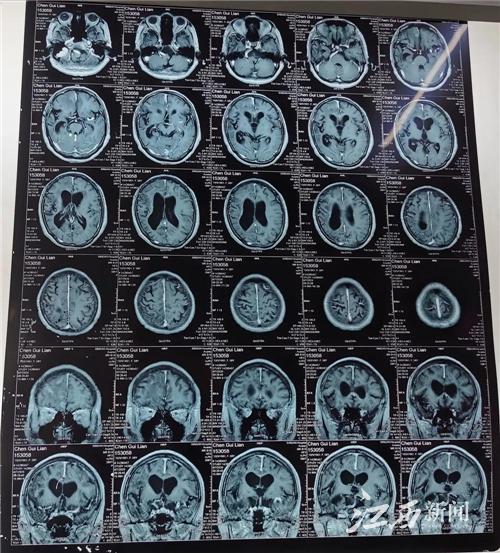

接診的徐春華聽(tīng)了癥狀描述后,立刻安排她做了進(jìn)一步磁共振檢查和腦電圖檢查,發(fā)現(xiàn)顱內(nèi)右側(cè)額葉有多個(gè)明顯的寄生蟲(chóng)肉芽腫病灶,癲癇放電也來(lái)自右側(cè)前頭部。

圖為2020年術(shù)前頭顱磁共振片

徐春華介紹,大腦受到散在多發(fā)的寄生蟲(chóng)病灶刺激和破壞,是引起癲癇發(fā)作的主要原因。